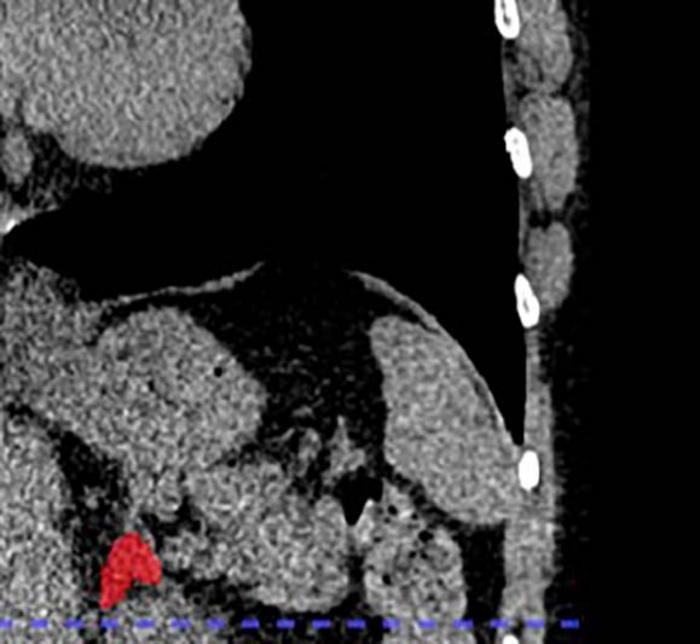

Y es que un equipo de investigadores liderado por la doctora Elena Ghotbi, del Johns Hopkins University School of Medicine, en Estados Unidos, entrenó un modelo de aprendizaje profundo para medir el volumen de las glándulas suprarrenales a partir de tomografías de tórax ya realizadas.

Dado que cada año se realizan decenas de millones de estas tomografías, la técnica tiene el potencial de aplicarse de forma masiva sin necesidad de nuevas pruebas. Gracias a este enfoque, se puede aprovechar información existente para evaluar la ‘carga biológica’ del estrés de forma objetiva.

Este hallazgo representa una verdadera innovación clínica: por primera vez es posible “ver” el estrés crónico acumulado en el cuerpo mediante una imagen médica habitual, en lugar de depender únicamente de cuestionarios o mediciones puntuales de cortisol.